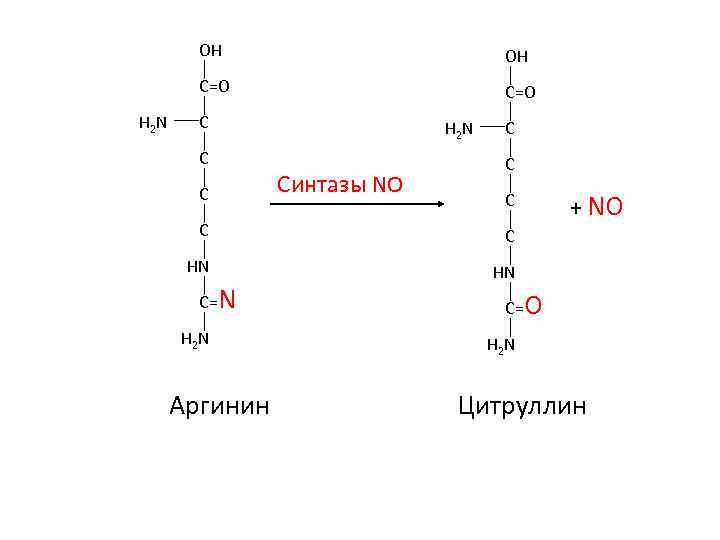

OH C=O H 2 N OH C=O C C C H 2 N Синтазы NO C C C HN + NO HN C=N H 2 N Аргинин C=O H 2 N Цитруллин